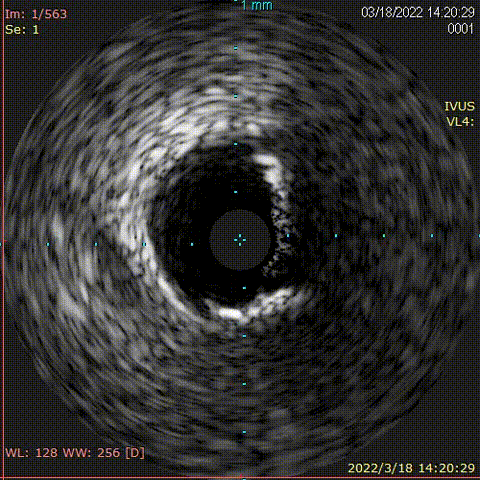

对前降支行IVUS,钙化较重,超声导管通过困难

旋磨后行IVUS查看,钙化较前明显减轻